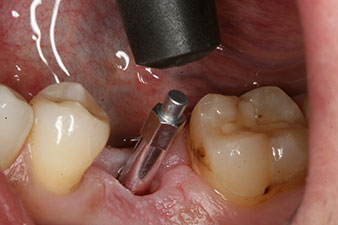

Fig. 3: After preparation with the Implantmed implantology motor, an implant (diameter 4 mm, length 12 mm) was screwed in by the motor at a torque of 43 Ncm.

The implant was placed as planned after thorough removal of the granulation tissue (blueSky, bredent).

The torque used for the machine-driven placement was 43 Ncm. In addition, after screwing a measuring post (SmartPeg) specially matched to the implant, the ISQ value was measured with the probe of the W&H Osstell ISQ module.